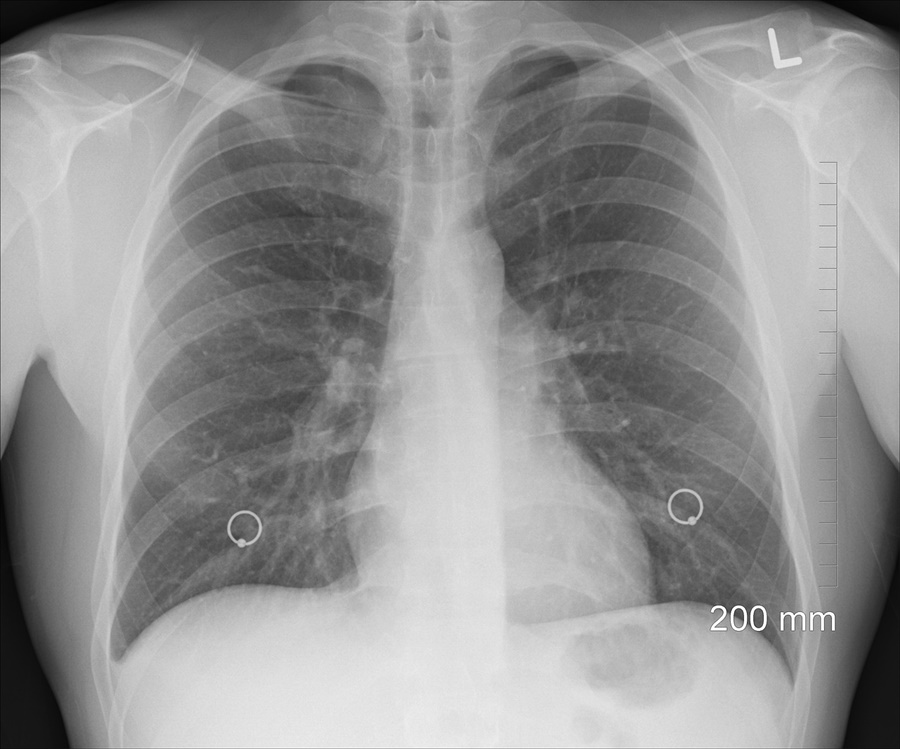

가래가 생기는 원인은 여러 가지가 있습니다. 가장 일반적인 원인 중 하나는 감염입니다. 감염성 질환이 있을 경우, 우리 몸은 기도를 보호하기 위해 가래를 생성합니다. 아래 도표는 가래가 생기는 주요 원인을 정리한 것입니다.

가래는 다양한 감염성 질환과 관련이 있습니다. 이러한 질환들은 호흡기계에 영향을 미치며, 각각의 증상과 원인이 다릅니다. 다음은 감염성 질환의 종류를 정리한 도표입니다.